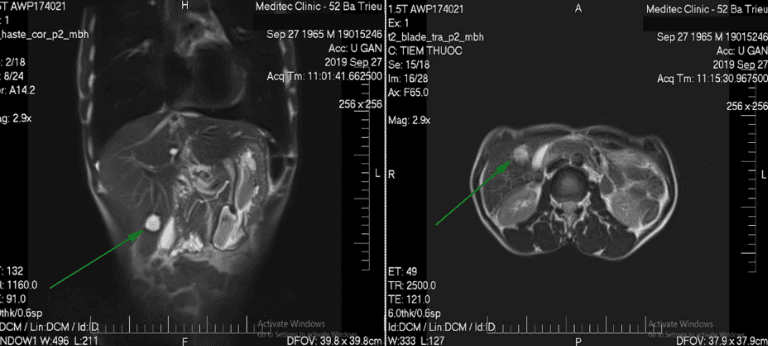

Chụp cộng hưởng từ (MRI) ổ bụng là phương pháp Chẩn đoán hình ảnh rất cần thiết trong những bệnh lý nghi ngờ tổn thương ở ổ bụng vì hình ảnh từ MRI có độ tương phản tốt, độ phân giải cao, hình ảnh rõ nét giúp bác sĩ dễ dàng đánh giá được tổn thương. Hơn nữa, chụp cộng hưởng từ MRI còn có khả năng tái tạo hình ảnh 3D, dựng hình cấu trúc giải phẫu cần đánh giá giúp nâng cao khả năng chẩn đoán bệnh lý.

● Các bệnh lý hệ tiết niệu: Khảo sát thận, niệu quản và khối u sau phúc mạc, phát hiện u thận, đánh giá trước mổ các khối u thận bao gồm cả đánh giá tĩnh mạch thận và tĩnh mạch chủ dưới. Đánh giá đường niệu đối với các bất thường giải phẫu (MR urography). Theo dõi sau phẫu thuật, can thiệp khối u thận.